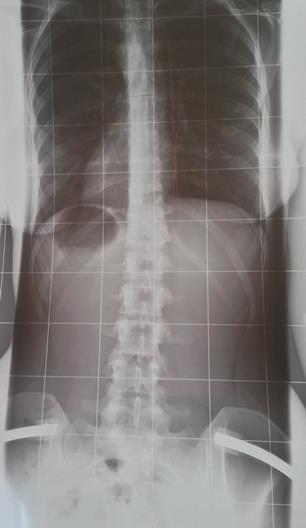

Soo ich melde mich noch einmal, da ich heute bei Dr. Hoffmann war..

Bin immer noch ein bisschen "geschockt" über das Ergebnis, dachte das es besser ausfaellt, hab es wohl zu lange verdraengt :rolleyes:

Es sind jetzt 61° Kyphose, 6° Skoliose und ein leichter Beckenschiefstand

Für den Beckenschiefstand habe ich Einlagen verschrieben bekommen; die leichte Skoliose kommt wohl durch den Ausgleich des schiefen Beckens zustande und sei wohl nicht weiter schlimm.

Zur Kyphose meinte Dr. Hoffmann, dass ich sei noch sehr beweglich sei und da ich bis jetzt auch keine Schmerzen habe meinte er, dass eine Theraphie nach Schroth erst einmal völlig ausreichend sei. Darum werde ich mich dann morgen auch sofort kümmern.

Zusatzlich meinte er, dass es wohl ein leichter (?) Scheuermann sei, was man wohl an den Wirbeln sieht..

Habe euch mal die Bilder angehaengt; wo sieht man das denn? War leider bei dem Termin selbst ziemlich durch den Wind durch die Diagnose und hab diverses vergessen zu fragen :rolleyes:

Und sieht man denn da jetzt auch eine Hyperlordose oder nur eine Hyperkyphose?

Allgemein kam es mir bei ihm so vor, als ob er der Meinung war, dass das nun wirklich nicht sonderlich schlimm sei.. ja da machen wir ein bisschen Krankengymnastik, da brauchen sie sich nicht in ein Korsett zwaengen, das wird dann schon wieder - so nach dem Motto. Liegt das daran, dass scheinbar noch alles ziemlich beweglich zu sein scheint? Weil nach so wenig hört sich 61° meiner Meinung nach jetzt nicht an, und das seitliche Röntgenbild find ich auch sehr gruselig :rolleyes:

Dateianhänge

1.jpg

1.jpg (18.25 KiB) 17969 mal betrachtet

2.jpg

2.jpg (23.35 KiB) 17969 mal betrachtet

Der Ausdruck "ein leichter Scheuermann" ist mir aus dem Mund von Dr. Hoffmann auch neu. Es gibt in der Umgangssprache den Begriff "ich habe einen Scheuermann" und dann mit dem Begriff "leicht" die Tatsache, dass der nicht so ausgeprägt sei, womit man in der Regel die dadurch entstandende Hyperkyphose/Hyperlordose bezüglich Winkel meint.

Das trifft hier aber nicht zu, sodass ich vermute, dass Dr. Hoffmann Keilwirbel meint, die es bei Dir wohl nicht gibt. Ein weiteres Merkmal für einen abgelaufenen Scheuermann sind die Schmorlschen Knötchen, die er wahrscheinlich im Röntgenbild gesehen hat. Für die eigentliche Behandlung sind aber nur Keilwirbel relvant, die eine Korrektur erschweren können.

Ich sehe da schon eine Hyperlordose (Hohlkreuz) als Ausgleich zur Hyperkyphose.